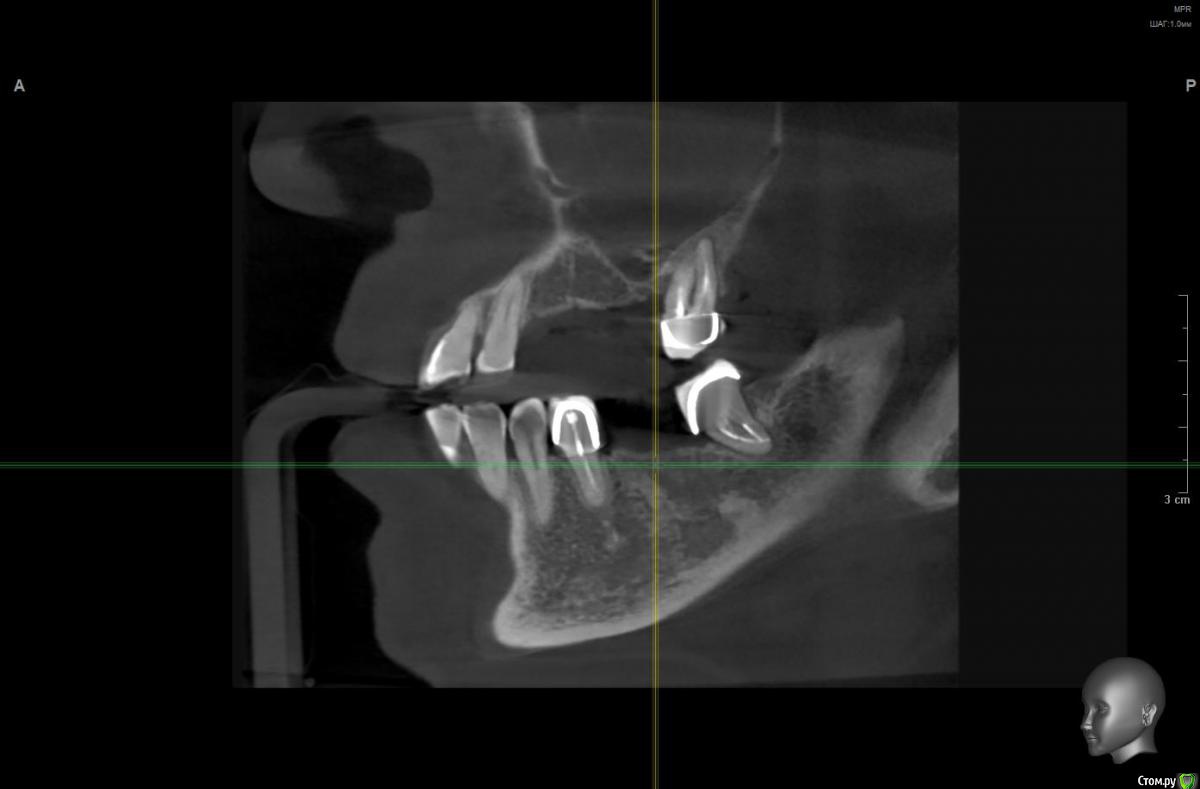

Great Teacher Опубликовано 7 апреля, 2018 Поделиться Опубликовано 7 апреля, 2018 Уважаемые врачи!Что бы Вы посоветовали сделать в данной ситуации (файл с КТ http://fayloobmennik.cloud/7240065).Была на приеме у двух специалистов: один говорит о том, что справа внизу атрофия костной ткани и возможны только маленькие импланты, но есть опасность близости к нерву, верх - только после эндоскопической гайротомии. Второй специалист утверждает, что внизу справа никаких проблем нет, и можно установить обычные импланты. Меня также очень интересует, возможно ли в данной ситуации поставить скуловые импланты зигома или all-on-three Trefoil с немедленной нагрузкой? С нетерпением жду совета специалистов и надеюсь на Вашу помощь! Ссылка на комментарий

wladdX Опубликовано 9 апреля, 2018 Поделиться Опубликовано 9 апреля, 2018 Несколько скриншотов 2 Ссылка на комментарий

Irouil Опубликовано 10 апреля, 2018 Поделиться Опубликовано 10 апреля, 2018 1. Внизу справа можно имплантироваться, мягкотканную пластику провести нужно будет только 2. В пазухе слева живёт грибок, надо удалять независимо от вида имплантации на верхней челюсти 3. Про зигомы надо ещё КТ самих скул 4. С трефоилом знаком только по наслышке, но он используется (вроде бы) только на нижней челюсти, там необходимости его я не вижу. Коллеги, что знакомы с ним лучше, могут поправить. 1 Ссылка на комментарий

Irouil Опубликовано 10 апреля, 2018 Поделиться Опубликовано 10 апреля, 2018 Спасибо,уважаемые доктора,в пазухе слева дентин.Там пломбировочный материал, возможно искусственный дентин, грибковое тело растет на немА мягкотканная пластика проводится одновременно с установлением имплантов?ДаДля установки имплантов внизу справа сколько их нужно и должны ли они быть меньшего размера из-за атрофии костной ткани?Меньшего чем что? Чем Ваша челюсть? безусловно. В остальном, по моему мнению, установить Вам имплантаты с покрывающими необходимости размерами особых препятствий нет. Нужно два имплантата установить. А импланты внизу слева- сколько их нужно- один или два? С нетерпением жду ответа.Зависит от того, сколько и что будет наверху. 1-2 1 Ссылка на комментарий

Bier Опубликовано 11 апреля, 2018 Поделиться Опубликовано 11 апреля, 2018 я бы думал про установку по паре имплантатов с каждой стороны на каждой челюсти. Слева внизу не вижу состояния зуба, скриншота нет.Внизу справа можно имплантировать, левую пазуху обязательно чистить.О зигомах или трефойле думать рановато, это радикальные вещи уже. Сначала пазуху почистить, потом поставить имплантаты внизу, потом заниматься верхом. 1 Ссылка на комментарий